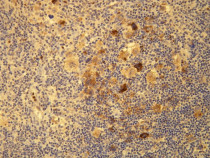

anti-EBV LMP1 antibody [D24-G] for IHC-Formalin-fixed paraffin-embedded sections and EBV

检测图片 (1) Click the Picture to Zoom In